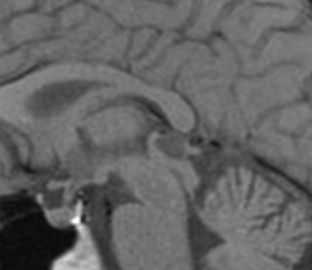

МРТ при кистах сосудистого сплетения головного мозга

Кисты сосудистого сплетения относятся к редким патологиям, обнаруживаемым случайно при МРТ или КТ головного мозга. Кисты в области сосудистого сплетения могут в норме наблюдаться у плода, но исчезают к 26 неделе беременности. Считается, что часть случаев связано с трисомией 18 хромосомы.

При КТ видна характерная кальцификация по краям кисты. При МРТ головного мозга киста представляет собой мелкие четко очерченные ликворные образования. Дифференциальную диагностику при МРТ головного мозга надо проводить с :

Ксантогранулема при МРТ головного мозга очень похожа на кисту сосудистого сплетения, но отличается смешанным содержимым из жира, коллоида, ликвора и продуктов крови. По этой причине на МРТ типа FLAIR они остаются видны. На диффузионно-взвешенных МРТ сигнал от ксантогранулемы яркий, в отличие от кист.

Гипертрофия сосудистого сплетения видна на МРТ головного мозга как его диффузное увеличение, нередко приводящее к гидроцефалии. Плексит - воспалительный процесс, сопровождающийся воспалением и гипертрофией сосудистого сплетения и сочетающийся с вентрикулитом и церебритом, именно их проявления, в первую очередь видны при МРТ головного мозга.